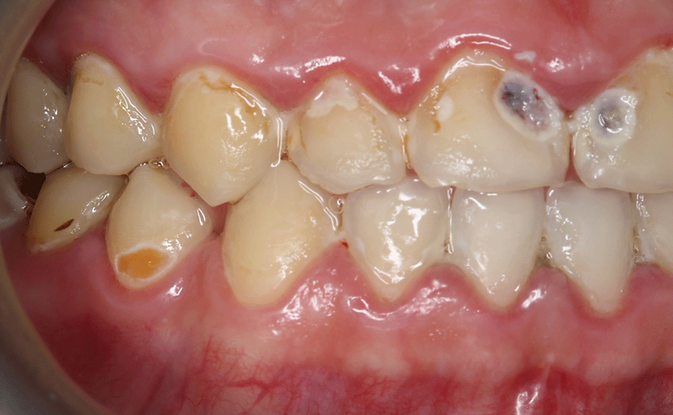

Tak jak w tym przypadku:

pacjent z nadwrażliwością w gabinecie

Tutaj młody człowiek z bardzo dużą ilością biofilmu, w badaniu czuć miękkie szkliwo. Liczne ubytki erozyjne, spowodowane nadmierną podażą substancji o odczynie kwaśnym. Ubytki próchnicowe, odwapnienia. Niedostateczna higiena związana z brakiem edukacji i dentofobią u pacjenta.

1. Usunęłam biofilm bakteryjny i założyłam mus Biosmalto na 2 minuty na łyżce.

2. Wyedukowałam pacjenta oraz wykonałam trening w ustach.

3. Dopasowałam miękką szczotkę manualna, nauczyłam prawidłowej techniki szczotkowania.

4. Zaleciłam odstawienie kwaśnych substancji.

5. Włączyłam do mycia zębów pastę Vitis Sensitiv, a na noc zastosowanie odżywki Tooth Mouses.

Właściwa wizyta na oczyszczenie kamienia została zaplanowana na za 2 tygodnie.  W takim przypadku odpuść, nic na siłę. Wrażliwość jest zbyt duża.

Praca skalerem na miękkim szkliwie powoduje dużo większe szkody. Zrób konieczne minimum.